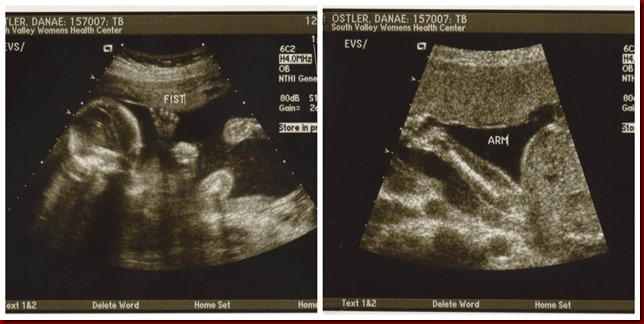

I told you I was getting beat up that morning! I guess he does not like the doctor either. What a spunky little guy. He still has this strong and fun (most of the time) personality today!

Covering his face with his arms and hands, before finally revealing his little cleft. I really do think he was looking out for his Mommy and her emotions. Bless that boy!